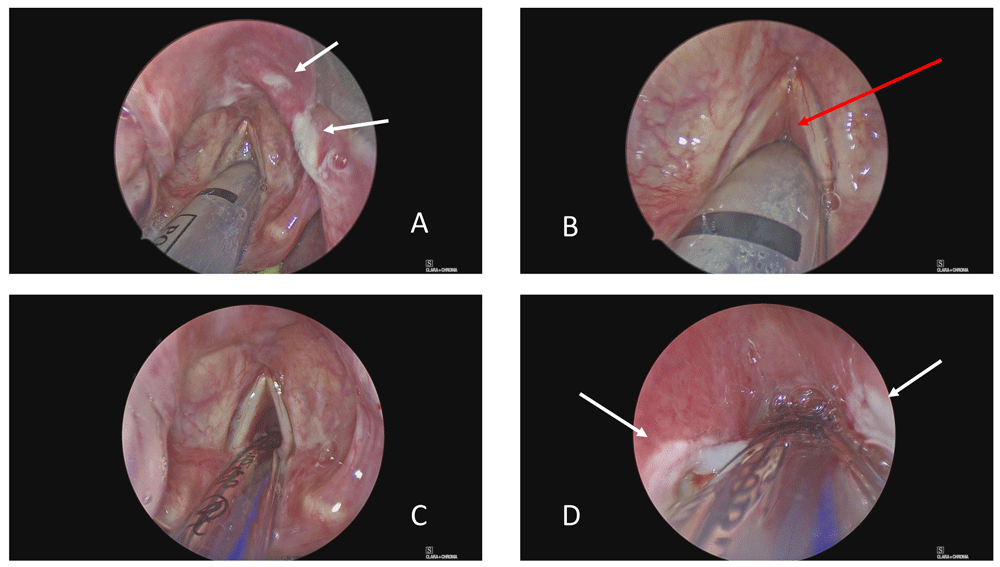

The epiglottis was inflamed with shallow, irregular, ulcers (Figure 2A). A sample of the ulcerated area was sent for microbiology testing. The rest of the supraglottis and superior surface of the vocal cords were spared, whilst profound oedema encased the ETT from cord level downwards (Figure 2B). It was not possible to pass the Hopkins’ rod past cord level. Adrenaline 1:10,000-soaked neurosurgical patties were packed around the tube in the glottic and subglottic area for 15 minutes to try and reduce swelling and risk of bleeding, and then removed using microlaryngeal instruments. Following pre-oxygenation and apnoea, a paediatric endotracheal tube bougie (10 ch × 600 mm, P3 Medical Ltd) was introduced through the ETT, the ETT was removed atraumatically with steady traction and a size 6 ETT then “railroaded” over the bougie (under direct rigid laryngoscopic) vision to replace it. Ventilation was recommenced without incident. Hopkins’ rod examination was now possible through the newly patent anterior glottis (Figure 2C), but only as far as the fourth tracheal ring due to upper tracheal and subglottic oedema. Ulcers were present bilaterally in the subglottis (Figure 2D). Depomedrone (40 mg/ml, 0.3 ml per side) was injected into the subglottis using a modified butterfly needle.

(A) View of supraglottis showing ulcerated epiglottis. (B) Glottis showing relative sparing of vocal cords and false cords, but profound subglottic oedema. (C) Following change to size 6 endotracheal tube, there is some anterior glottic airway. (D) However, the subglottis is also ulcerated and oedematous mucosa prevents rigid bronchoscopy (0o Hopkins’ rod) beyond the third tracheal ring. White arrows indicate areas of ulceration and red arrow subglottic oedema.